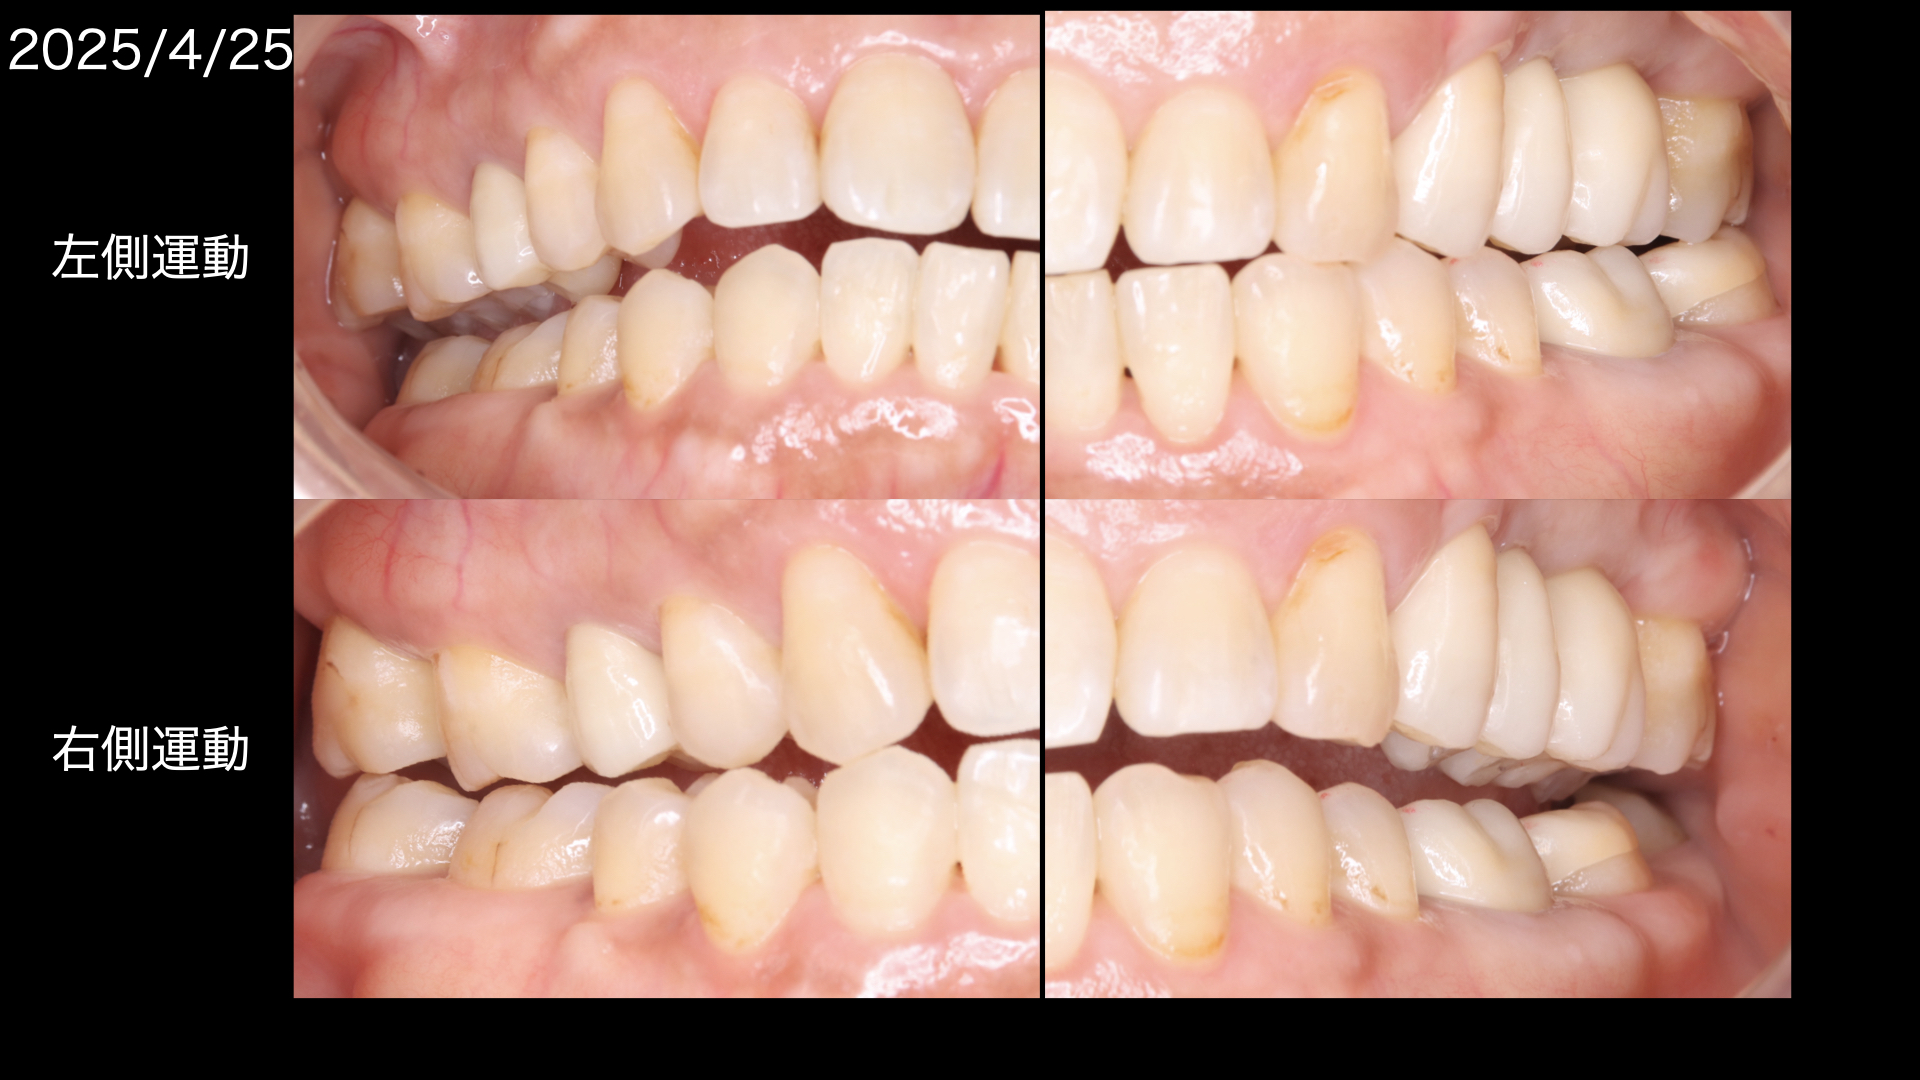

このように左側運動では左の犬歯(糸切り歯)だけが当たって、右側はあたらないように(離開:ディスクルージョン)

右側運動でも同じようになっており

治療前と違い、前歯が奥歯を守っている状態です。